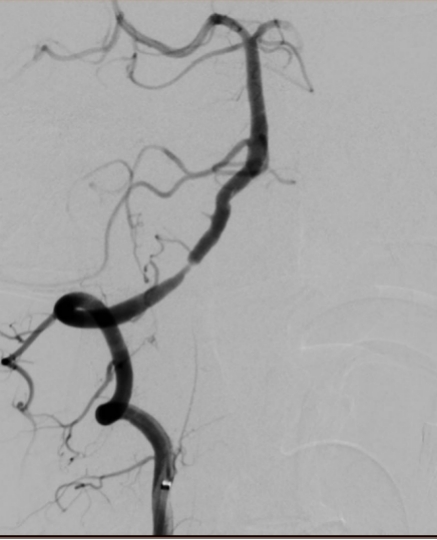

脑血管造影是目前脑血管检查的金标准,是通过动脉插管,使用造影剂显影完成脑血管检查的一种微创方法。其特点:简单、方便、安全、准确、创伤小。我院从2009年开始开展脑血管造影检查,目前开展经桡动脉、股动脉两种路径完成脑血管造影及治疗,桡动脉路径大大减轻患者的痛苦。目前开展的治疗手术:颅内外血管球囊扩张成形术、支架置入术、动脉瘤栓塞术、急症溶栓、取栓术,对于出血性脑血管病患者开展了微创血肿清除术。每年造影检查量约500例左右,治疗量约100例左右。介入技术水平走在了全市前列,取得了广大患者的好评。

图片1.jpg  图片2.jpg

经股动脉入路造影                                                               经桡动脉入路造影